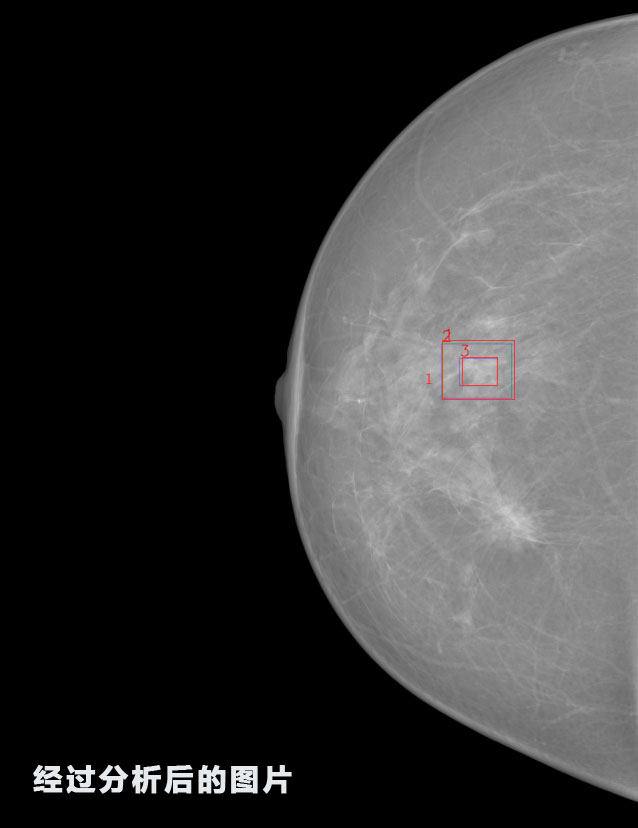

英特健康AI深度學習醫(yī)療圖像識別系統(tǒng)案例_乳腺

02.jpg

識別報告:

1.發(fā)現(xiàn)良性鈣化,可能性為19.88%---位置框指數(shù):[1796.0867 1359.8237 2058.1372 1582.5334]

2.發(fā)現(xiàn)惡意鈣化的可能性為15.18%---位置框指數(shù):[1789.4733 1365.9951 2063.7698 1576.0613]

3.發(fā)現(xiàn)惡意鈣化的可能性為12.45%---位于框指數(shù):[1859.3987 1422.3184 2006.5494 1528.2698]